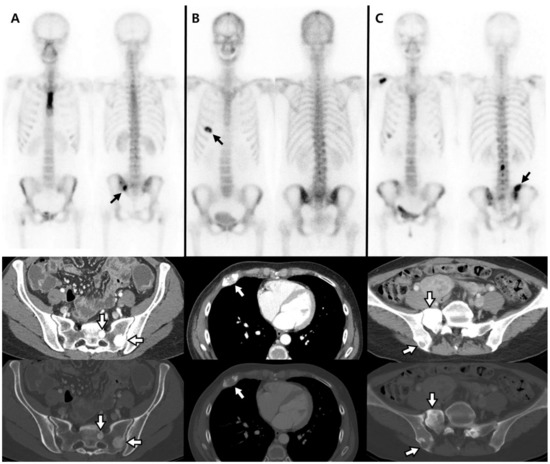

3. Results

3.2. Univariate Analyses for Distinguishing FP from Disease Progression

4. Discussion